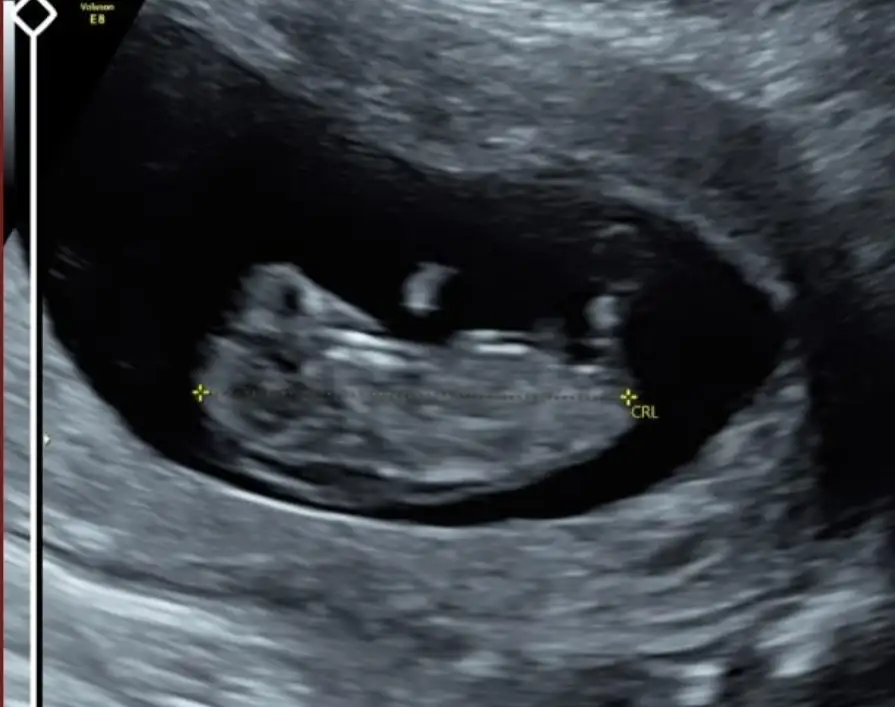

ManyakPrenses ManyakPrenses Merhabalar bende bir tahmin alabilirmym hem 8 hem 11. Hafta ektedir. Teşekkürler